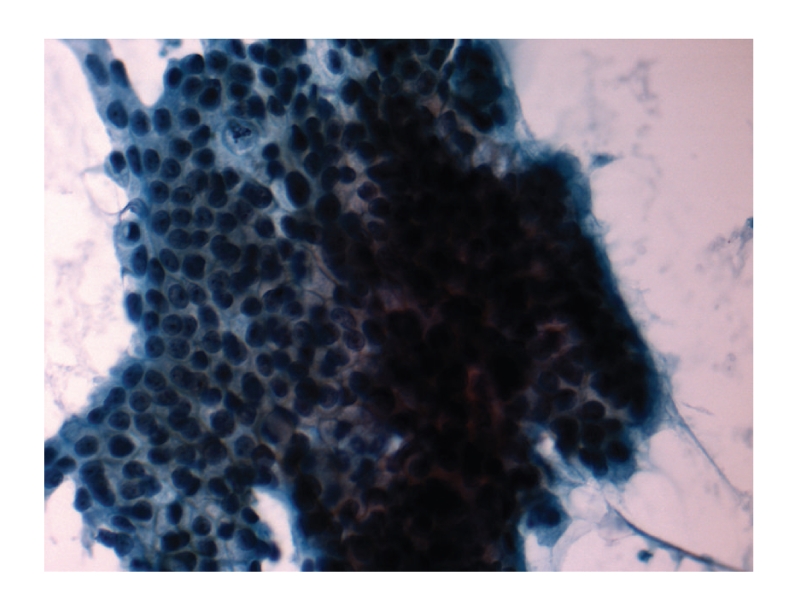

Figure 4.

Histological findings of the clavicle biopsy showing metastases pancreatic cancer.